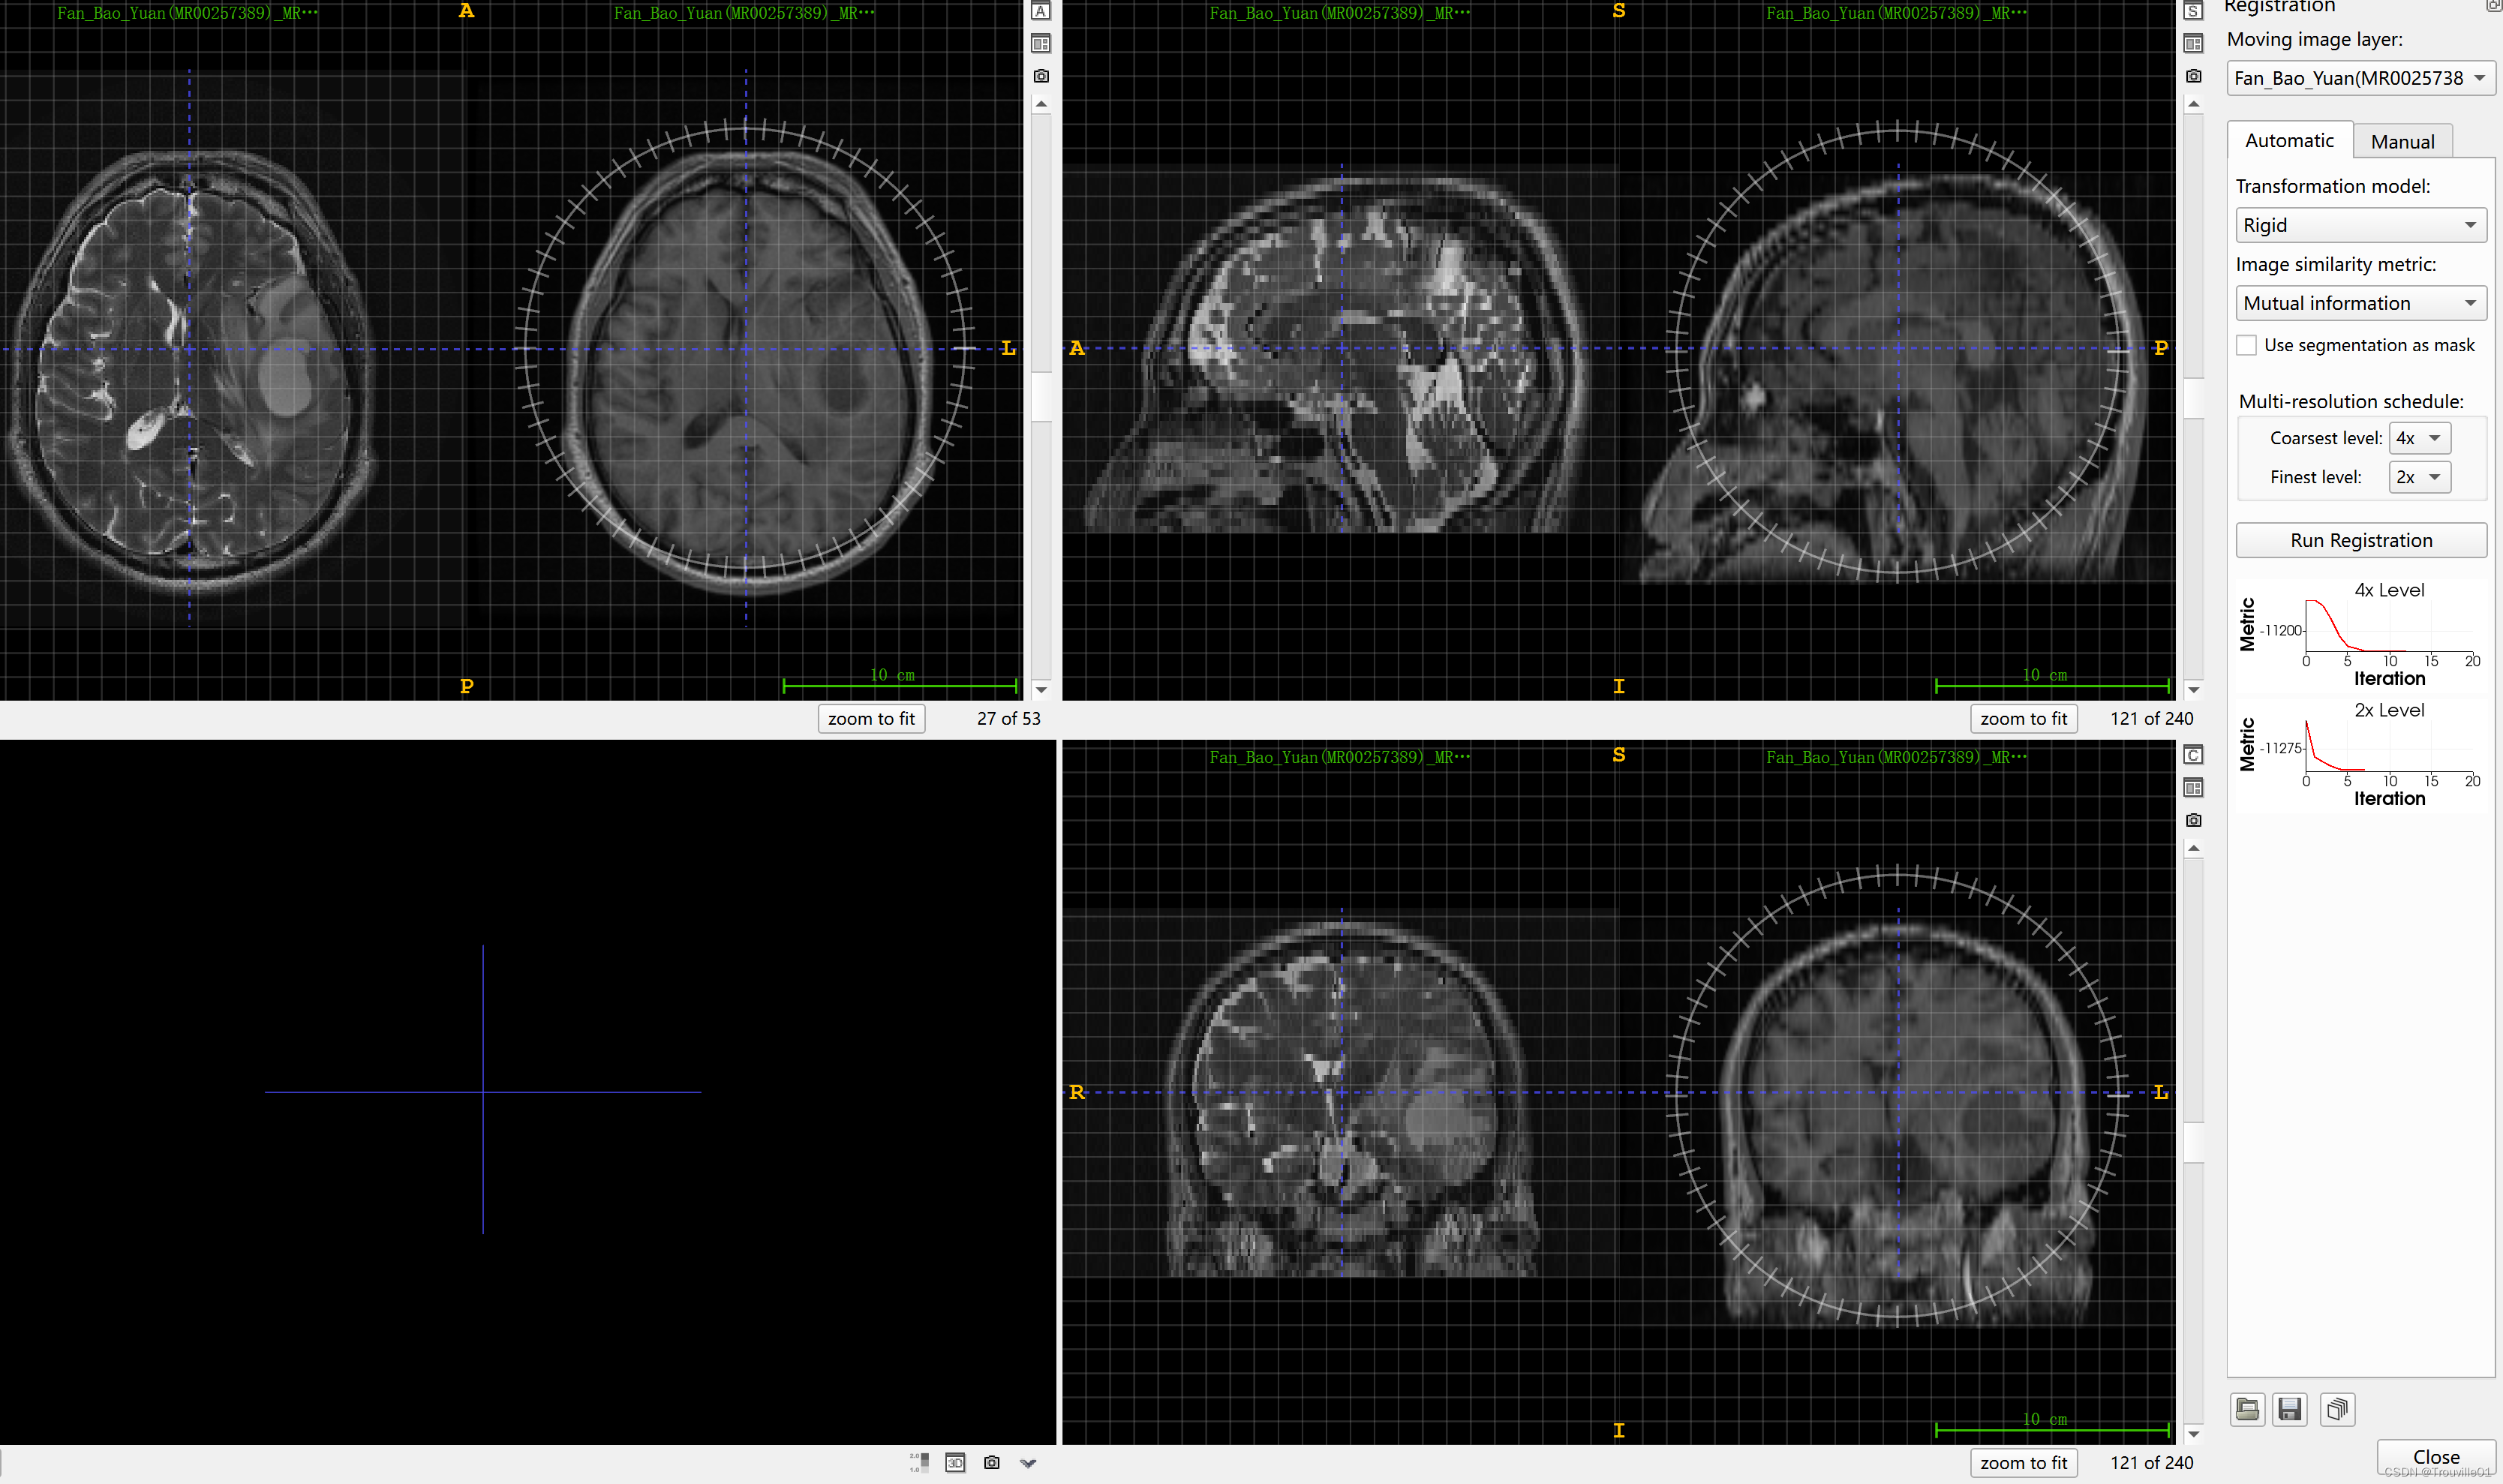

4. 点击tools,选择registration

5.选择右边菜单栏的Munal控件,选择Match by ,选择image centers,可以用来对齐图像,这步很关键!!!如果方向还是没有对齐,可以在图像上转动那个罗盘样的标尺来改变方向进行对齐。

6.选择automatic,run registration,到这里配准基本走完了,但是想要看到配准效果还得继续,